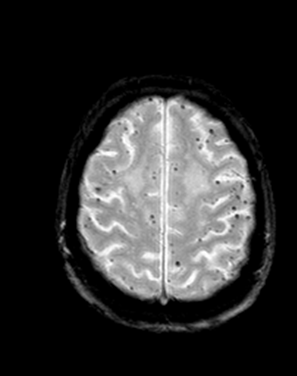

White matter lesions, old hemorrhages (hemosiderin) can only be depicted with MRI.

Multiple sclerosis typically appears with lesions presenting in the hemispheric white matter with a periventricular predilection. Other less usual locations for MS lesions include the cerebellum and the pons.

In the later stages the periventricular lesions can become confluent.

The method of choice for the imaging of multiple sclerosis is MRI. MS lesions secondary to their increased water content appear as increased signal intensity lesions on (T2 weighted), PD images and on FLAIR sequence.